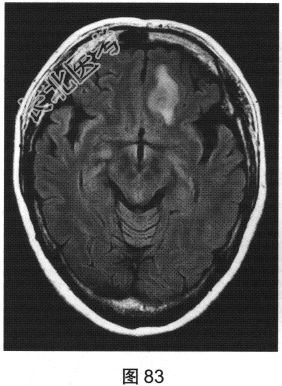

- 多项选择题2.[提示]患者行MRI检查,如图80~图85所示。患者MRI检查的阳性影像学表现包括( )

B、病变增强扫描未见明显强化

D、FLAIR呈稍高信号

E、病变增强扫描可见明显强化

G、MRI示左侧异常信号影

H、MRI示右侧异常信号影

- 多项选择题3.根据患者病史及影像学检查,提示其可能的诊断是( )

A、肉芽肿

B、特发性肥厚性硬脑膜炎

C、脑膜瘤

D、低级别星形细胞瘤

E、淋巴瘤

F、转移瘤